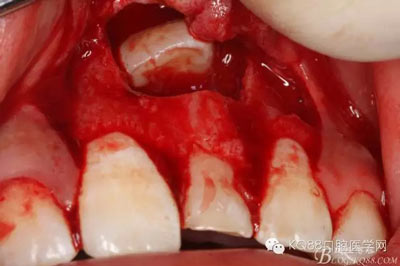

圖8.翻開牙齦粘膜瓣,可見左乳Ⅰ根方骨面隆起

圖9.超聲骨刀去除隆起的骨壁

圖10. 形成梯形骨縫